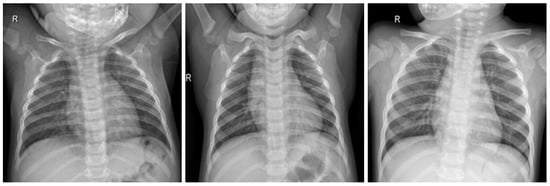

In this work, a COVID-19 radiography dataset collected in previous works related to a COVID-19 detection model [24,25] was used. The dataset contains X-ray lung images with four different classifications, which are COVID, Lung_OPACITY, Normal, and Viral Pneumonia. In this work, we utilized two classifications, which are COVID and Normal, focusing only on the COVID-19 detection machine learning process.

Figure 4.

COVID-19 negative X-ray image dataset samples.